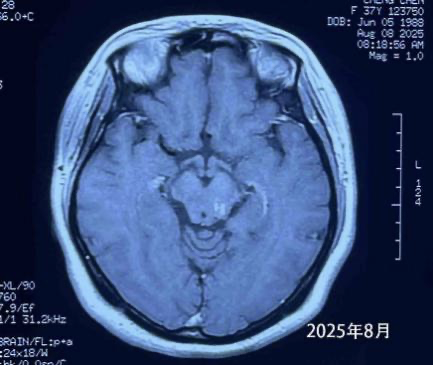

More than four years later, the patient remains in excellent condition, leading a normal life and working without restrictions. Dr. Wang emphasized the importance of regular MRI follow-ups. If small recurrences are detected, timely CyberKnife treatment can control progression. At her latest MRI check in August, the tumor had significantly shrunk.